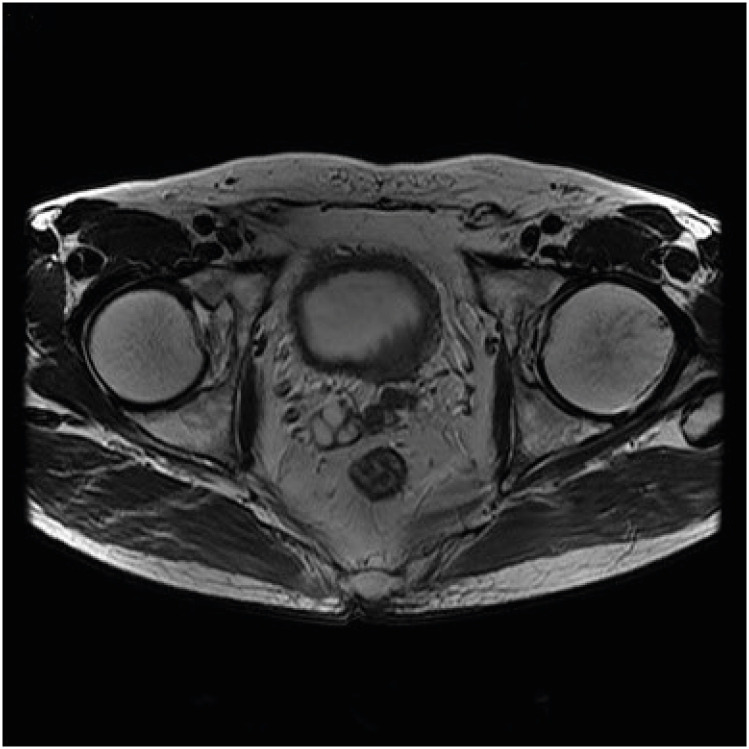

Case presentation: Patient A: A 61-year-old man worked as a city bus driver for approximately 17 years, from 2002 to 2019, and was exposed to night-shift work during this period. In March 2017, the patient was diagnosed with high-grade prostate cancer through core-needle biopsy after experiencing stinging pain lasting for 2 months. Patient B: A 56-year-old man worked as an electrician and an automated equipment operator in a cement manufacturing plant for 35 years from 1976 to 2013 and was exposed to night-shift work during this period. In 2013, the patient was diagnosed with high-grade prostate cancer through core needle biopsy at a university hospital because of dysuria that lasted for 6 months.

Abstract Image